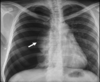

12

A

Consolidación alveolar